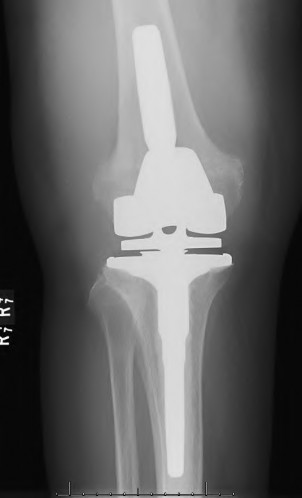

An 82-year-old woman falls and sustains the fracture shown in figure A. She denies any history of dislocation or prodromal pain prior to her fall. What is the most appropriate treatment?

The radiograph demonstrates a periprosthetic femur fracture extending to the tip of the stem. The long spiral fracture is consistent with a loose implant. The bone stock is sufficient. Therefore, this fracture pattern would classify as a B2 using the Vancouver classification system. The Vancouver classification for periprosthetic femoral fractures is simple yet incorporates all the pertinent factors such a location, stem fixation, and bone stock. Type A is a trochanteric fracture- lesser or greater. These can be treated non-operatively usually and ORIF if symptomatic. Type B fractures are around or just below the stem and are subdivided into three types. Type B1 is a fracture with a well fixed stem.

The treatment is cable plating or allograft struts or a combination of the two. Type B2 is a fracture with a loose stem with good bone stock. The treatment is a cementless porous coated long stem atleast two diameter length past the

fracture site. Type B3 is a fracture with a loose stem and comminution. For younger patients, use cementless porous coated long stems with allograft struts. For older patients, consider a tumor prosthesis. Cement fixation is sometimes necessary Type C is a fracture well below the stem tip. These can be treated independently of the prosthesis.